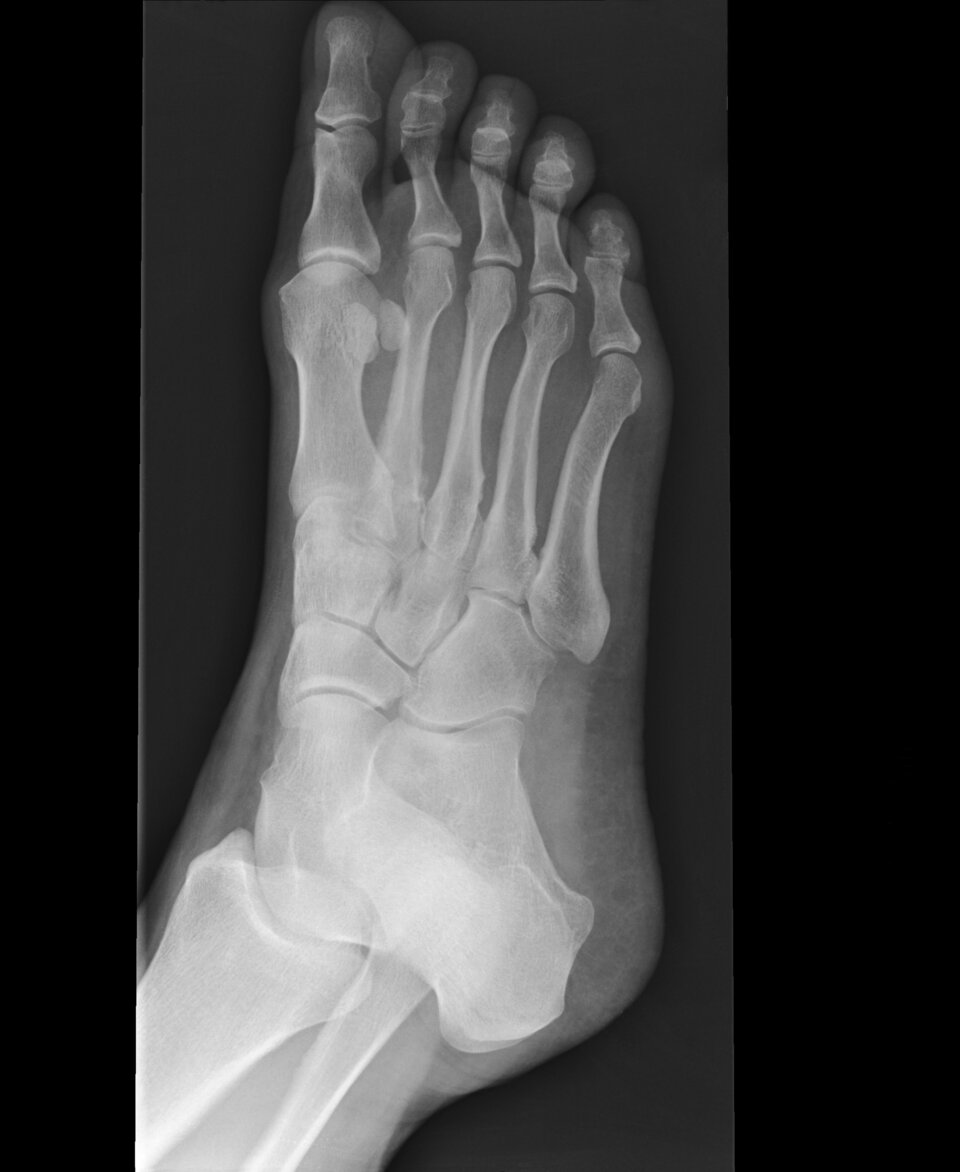

Stressfraktur des 2. Mittelfußknochens: Vor allem Läufer und Turner tragen ein erhöhtes Risiko.

Stressfraktur des 2. Mittelfußknochens: Vor allem Läufer und Turner tragen ein erhöhtes Risiko. © Science Photo Library / Marazzi, Dr. P.